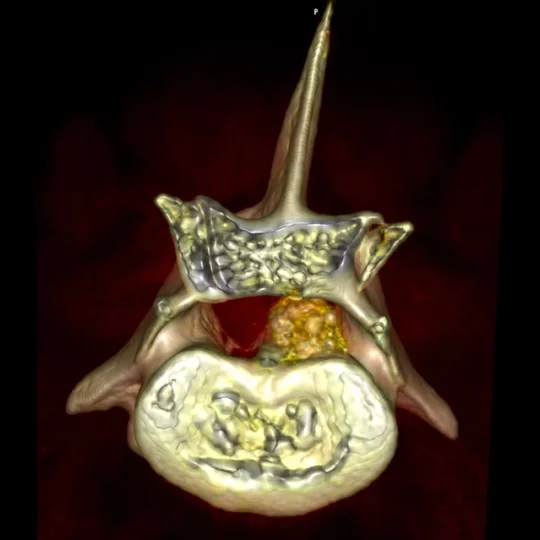

Tomografia komputerowa (TK) to nowoczesne, zaawansowane, bezinwazyjne i bezbolesne badanie diagnostyczne, które stanowi istotne uzupełnienie innych metod obrazowania, takich jak klasyczne RTG czy ultrasonografia. Dzięki wykorzystaniu w naszej klinice technologii TK możliwe jest uzyskanie precyzyjnych, trójwymiarowych obrazów wnętrza organizmu, co znacznie zwiększa skuteczność diagnostyki i pozwala na dokładniejszą ocenę stanu zdrowia pacjenta.

Tomografia komputerowa opiera się na serii ekspozycji promieniowania rentgenowskiego wykonywanych pod różnymi kątami. Uzyskane dane są następnie przetwarzane przez zaawansowane oprogramowanie komputerowe, które tworzy trójwymiarowy obraz badanej okolicy. W przeciwieństwie do tradycyjnego RTG, gdzie struktury nakładają się na siebie, TK pozwala na precyzyjne zobrazowanie poszczególnych warstw anatomicznych, co znacznie poprawia jakość diagnostyki.

- w niektórych przypadkach także tkanek miękkich (np. mózg, narządy jamy brzusznej, guzy nowotworowe, zmiany zapalne).